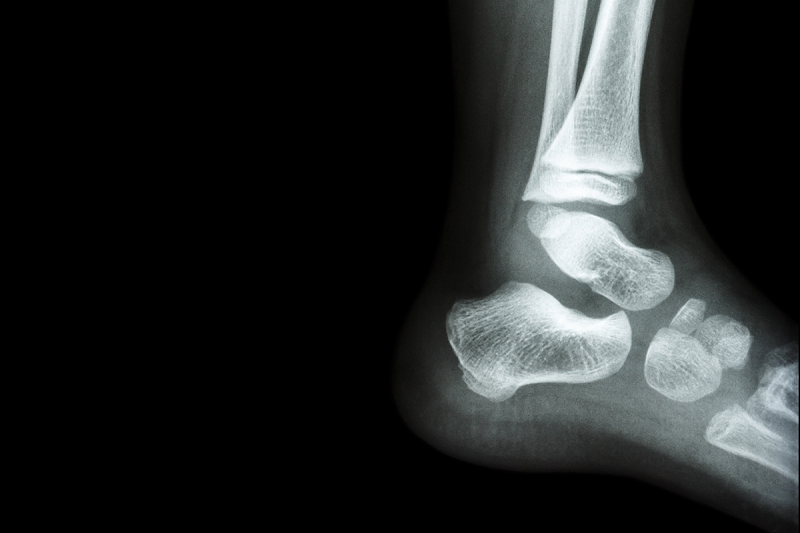

An x-ray of an ankle.

With the warmer weather upon us, we can expect an increase in paediatric ankle injuries coming to emergency departments. However, the vast majority are low-risk, soft-tissue injuries (i.e., sprains), or clinically minor fractures that have been shown to heal without specific intervention or orthopaedic follow-up. A common approach to investigating ankle injuries is to obtain an X-ray to look for a fracture, but new SickKids-led research shows there’s a better alternative that also uses less time and fewer resources.